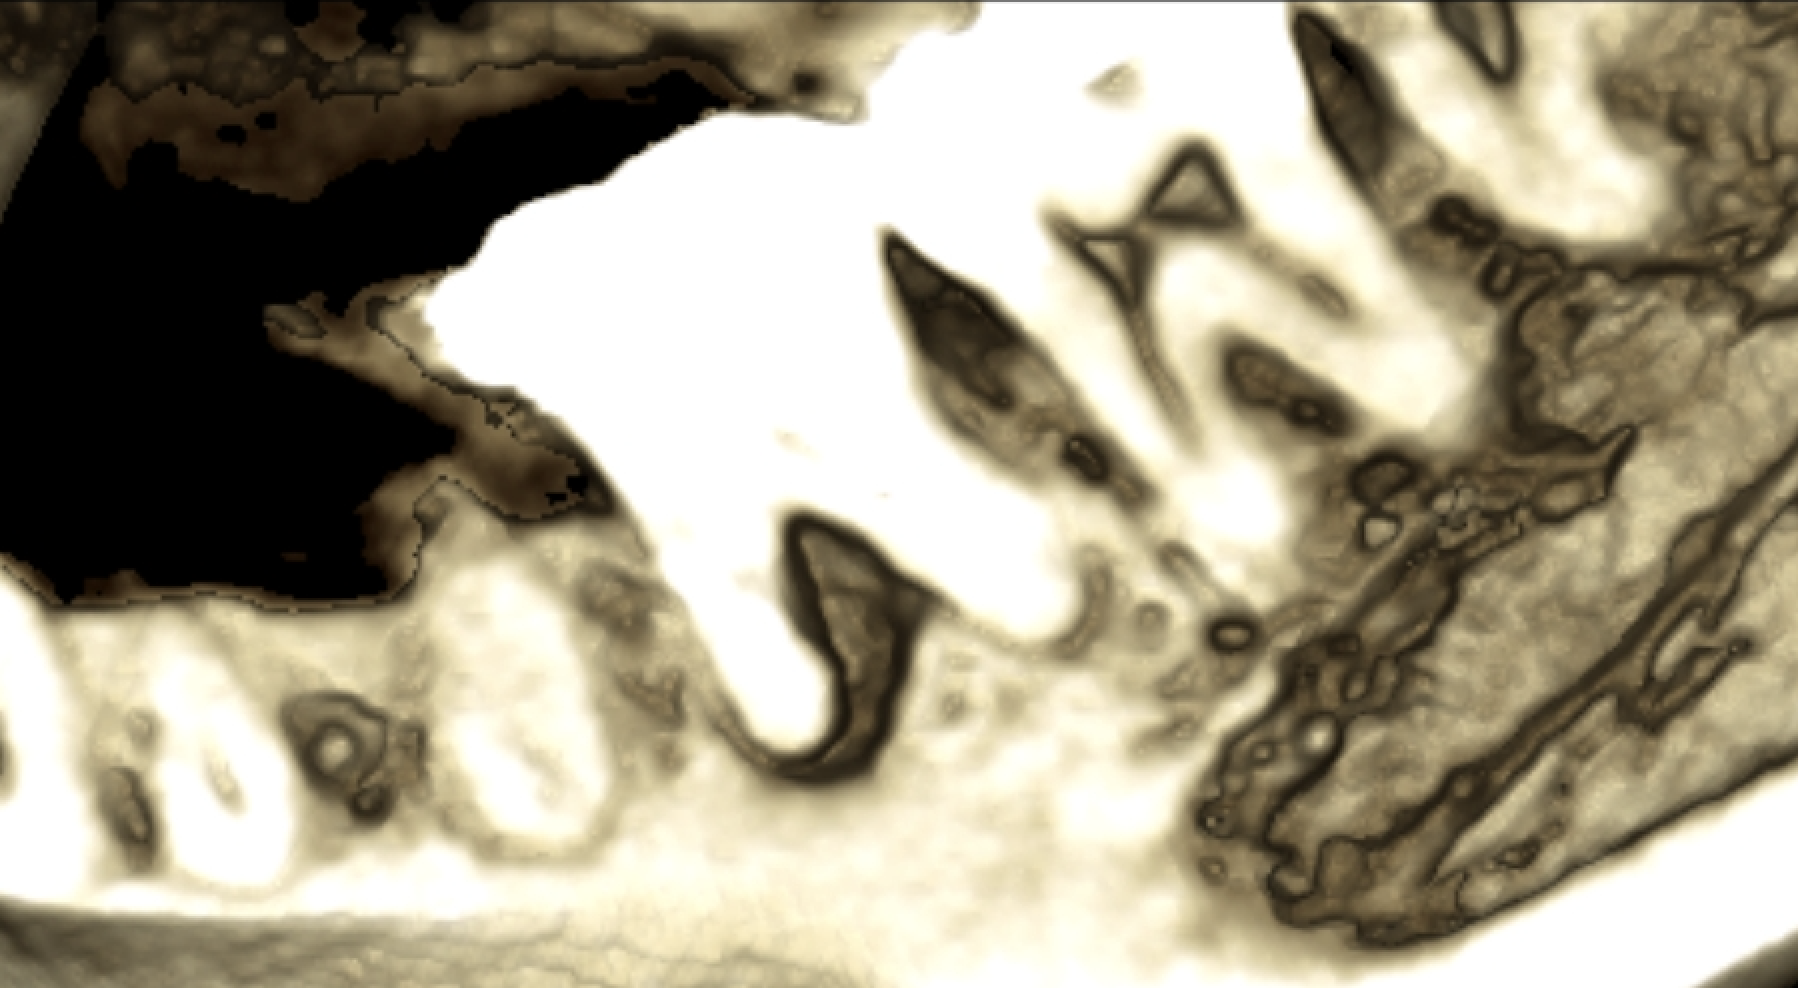

写真は同一部位のレントゲン写真とCT画像です。レントゲン写真は顎骨の形態や走行する神経の位置、歯が生えている方向把握することはできても2次元的な位置関係でしか把握できません。つまり歯や神経の位置がわかっていても実際にどのくらいの位置関係にあるのかを正確に判断することはレントゲン写真では不可能なわけです。しかし、歯科用CT画像では顎骨の形態や走行する神経の位置、歯の生えている方向、さらには骨密度の状態を3次元的に画像化する事が可能なため、より正確な診断する事ができます。

CTとはComputed Tomographyの略で、コンピューター断層撮影法という意味です。歯科用CTは医療現場で用いられているCT技術を歯科分野に応用した機械であり、X線を使って身体の断面を撮影して3次元的に画像化します。歯科の領域では特に頭頸部の画像化に特化して診断や治療に役立てられています。